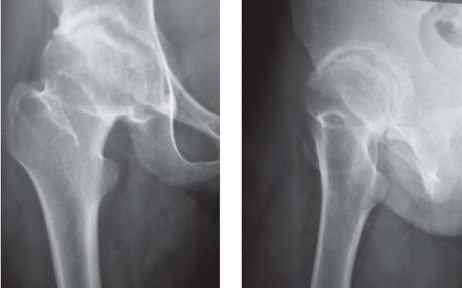

تُقدم تصاميم الجذع القصير خيارًا محافظًا لاستبدال مفصل الفخذ الكلي، حيث تحافظ على العظم والأنسجة الرخوة، وتُعد مناسبة للمرضى الشباب والنشطين الذين يعانون من التهاب مفصل الفخذ الموهن. يُنسب مفهوم جراحة استبدال مفصل الفخذ الكلي التي تحافظ على عنق الفخذ إلى مايكل فريمان. وقد اقترح ليو وايتسايد وتاونلي مفهومًا مشابهًا يدعو إلى الحفاظ على عنق الفخذ باستخدام جذوع تقليدية. أظهر وايتسايد وزملاؤه في دراسة على الجثث أن الحفاظ على 50% أو أكثر من عنق الفخذ يساعد في مقاومة القوى الالتوائية في الجذع المثبت قربيًا. كما أظهرت دراسة أجراها جاستي وزملاؤه على الكلاب، باستخدام جذوع مثبتة قربيًا مع جذع بعيد مصقول، أن المكون الديافيزي للجذع يوفر ثباتًا أوليًا ولكنه ليس ضروريًا لاستقرار الزرعة على المدى الطويل بمجرد تحقيق الاندماج العظمي القريب. وقد أدى ذلك إلى تطوير جذوع قصيرة تثبت في منطقة الميتافيزال.

تتوفر الجذوع القصيرة التي تحافظ على عنق الفخذ منذ عام 1985، مع مفصل Mayo (برنارد إف موري) الذي يتمتع بسجل حافل ممتاز على المدى الطويل. ومع ذلك، ليست جميع الجذوع القصيرة متشابهة، وتتوفر حاليًا خمسة تصاميم رئيسية. تشمل هذه التصاميم جذوعًا مستوحاة من مفصل Mayo (مثل METHA، ESKA، NANOS)، وجذوعًا قصيرة وضخمة ولكنها لا تحافظ على عنق الفخذ مثل Proxima، وجذوعًا منحنية تحافظ على عنق الفخذ (CFP: Pipino)، وجذوعًا مخروطية قصيرة (Taperlock Microplasty, Trilock)، وما يسمى بـ "قرون العنق" مثل BMHR و Silent hip.

لقد تم التساؤل عن دور الجذوع القصيرة في جراحة استبدال مفصل الفخذ الكلي. وتُقارن بشكل واضح مع جراحة إعادة تسطيح المفصل (hip resurfacing) وجذوع الفخذ المخروطية الحديثة غير الإسمنتية ذات نقل الحمل القريب. بينما تحافظ جراحة إعادة تسطيح المفصل على العظم، إلا أنه لا يمكن القول إنها تحافظ على الأنسجة الرخوة، حيث يكون الشق الجراحي ومدى تشريح الأنسجة الرخوة اللازم للتعرض عادة أكبر مما هو عليه في جراحة استبدال مفصل الفخذ التقليدية. علاوة على ذلك، تقتصر جراحة إعادة تسطيح المفصل على مفصل المعدن على المعدن، والذي له مجموعة مشاكله الخاصة مثل فرط الحساسية، والتهاب الأوعية الليمفاوية المرتبط بالمعادن (ALVAL)، ومشاكل الاستخدام لدى الشابات في سن الإنجاب، والمخاوف بشأن ارتفاع مستويات أيونات المعادن في الدم.

تم توثيق نتائج ناجحة باستخدام جذوع مخروطية مع زرعات تحميل الميتافيزال. إن الزرعات القصيرة المثبتة في الميتافيزال تحافظ على العظم، ويمكن زرعها باستخدام نهج جراحي طفيف التوغل، ويمكن استخدامها مع مجموعة متنوعة من أسطح الاحتكاك. مقارنة بجذوع الفخذ التقليدية، فإن زرعات الجذع القصير أكثر فسيولوجية، أي أنها توفر تحميلًا قريبًا، ولا تسبب ألمًا في الفخذ، ويسهل مراجعتها إلى استبدال مفصل الفخذ التقليدي. ومن ثم، فإن زرعات التحميل الميتافيزي القصير تعمل كجسر بين جراحة إعادة تسطيح المفصل والجذوع غير الإسمنتية القياسية، وهي مناسبة للمرضى الشباب الذين يعانون من التهاب المفاصل ولديهم عظم جيد النوعية.